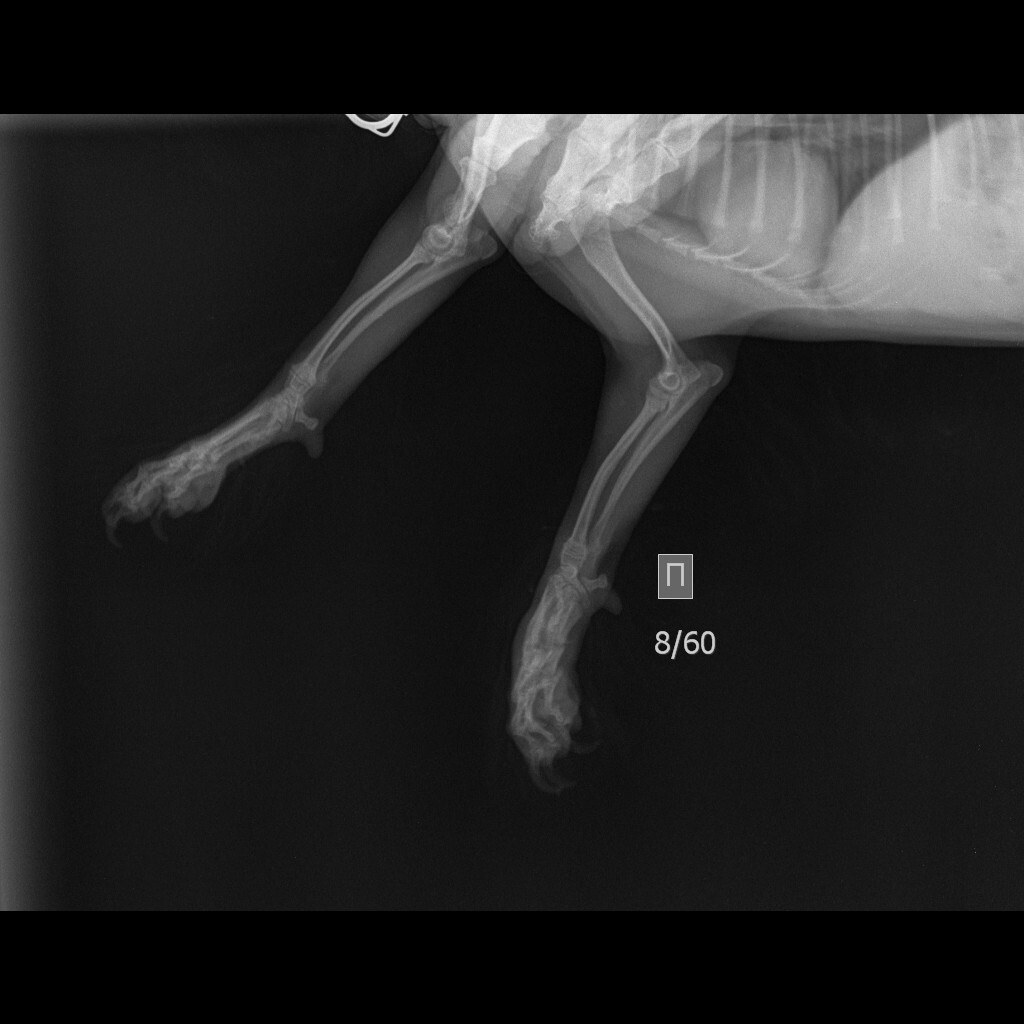

Вопрос вот в чем, щенок йоркширского терьера сломал 4 пальца на лапке. Ветеринарная клиника нашего небольшого города рекомендует делать операцию. Другой врач, в клинике побольше советует ничего не делать. Кому верить?

Вот на этом снимке хорошо виден перелом